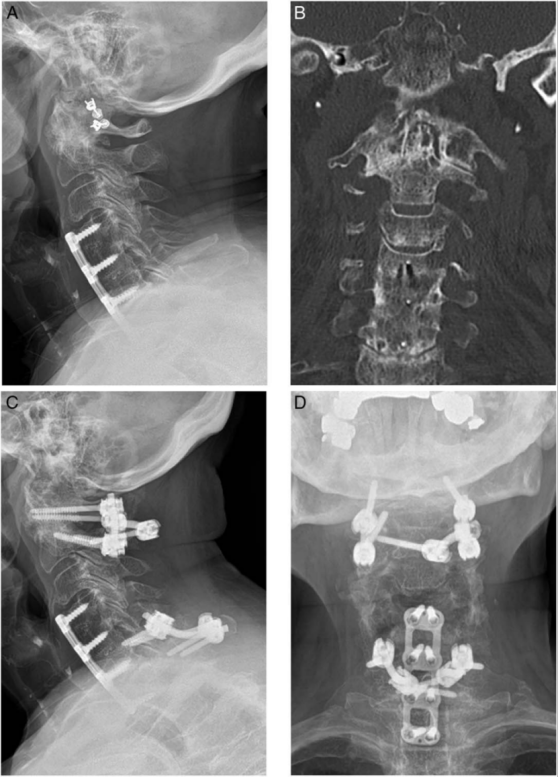

图 1 一名 47 岁女性,C1/C2 后路内固定融合术后不愈合伴螺钉松动的影像学资料。

(A)颈椎侧位 X 线片显示 C1/C2 螺钉周围出现透亮带,提示内固定松动;

(B)C1 轴位 CT 证实双侧 C1 螺钉周围透亮带;

(C)颈椎侧位 X 线片显示植入大直径螺钉并在 C3 增加固定;

(D)轴位 CT 显示 C1 大直径螺钉及 C1 环植骨。